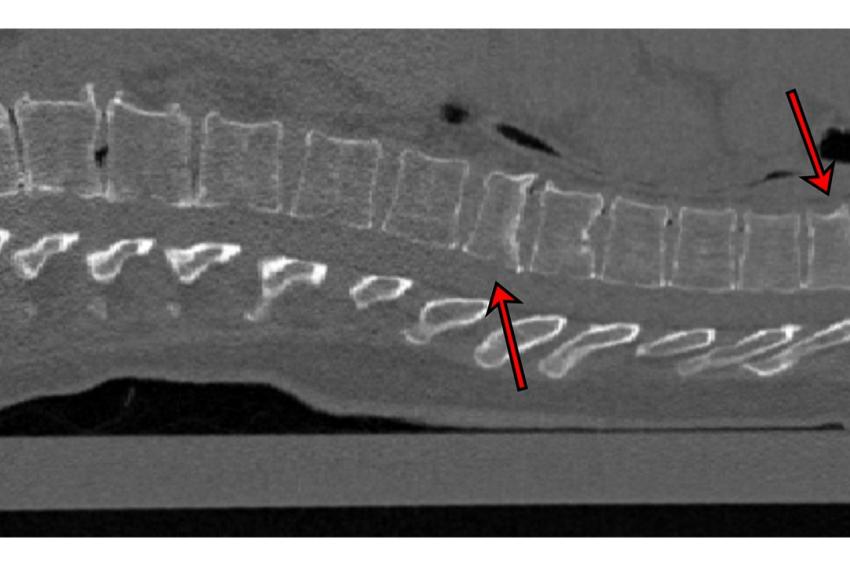

Oft werden CT-Bilder vom Brustkorb aufgenommen, um zum Beispiel die Lunge anzuschauen. Die Wirbelsäule ist zwar auf dem Bild zu sehen, wird aber nicht geprüft, weil ein anderes Problem im Vordergrund steht. „Unser Programm kann bei solchen Untersuchungen im Hintergrund laufen. Es schaut sich automatisch die Wirbelsäule an und gibt einen Hinweis auf Frakturen der Wirbelkörper, die ansonsten vielleicht nicht entdeckt worden wären“, erklärt Erstautor Yilmaz. Das ist wichtig, denn das Vorhandensein von Wirbelfrakturen erhöht das Risiko weiterer Brüche erheblich. Die Software arbeitet mit neuronalen Netzen. An 159 CT-Bildern der Wirbelsäule, die aus sieben Krankenhäusern Deutschlands stammten, wurde die KI getestet. Erfahrene Radiologen begutachteten zuvor die Bilder und entdeckten 170 Frakturen. „90 Prozent der Fälle mit Frakturen klassifizierte das neuronale Netz korrekt sowie 87 Prozent der Wirbel ohne Frakturen“, berichtet Yilmaz.

Schweregrad des Bruchs differenzieren